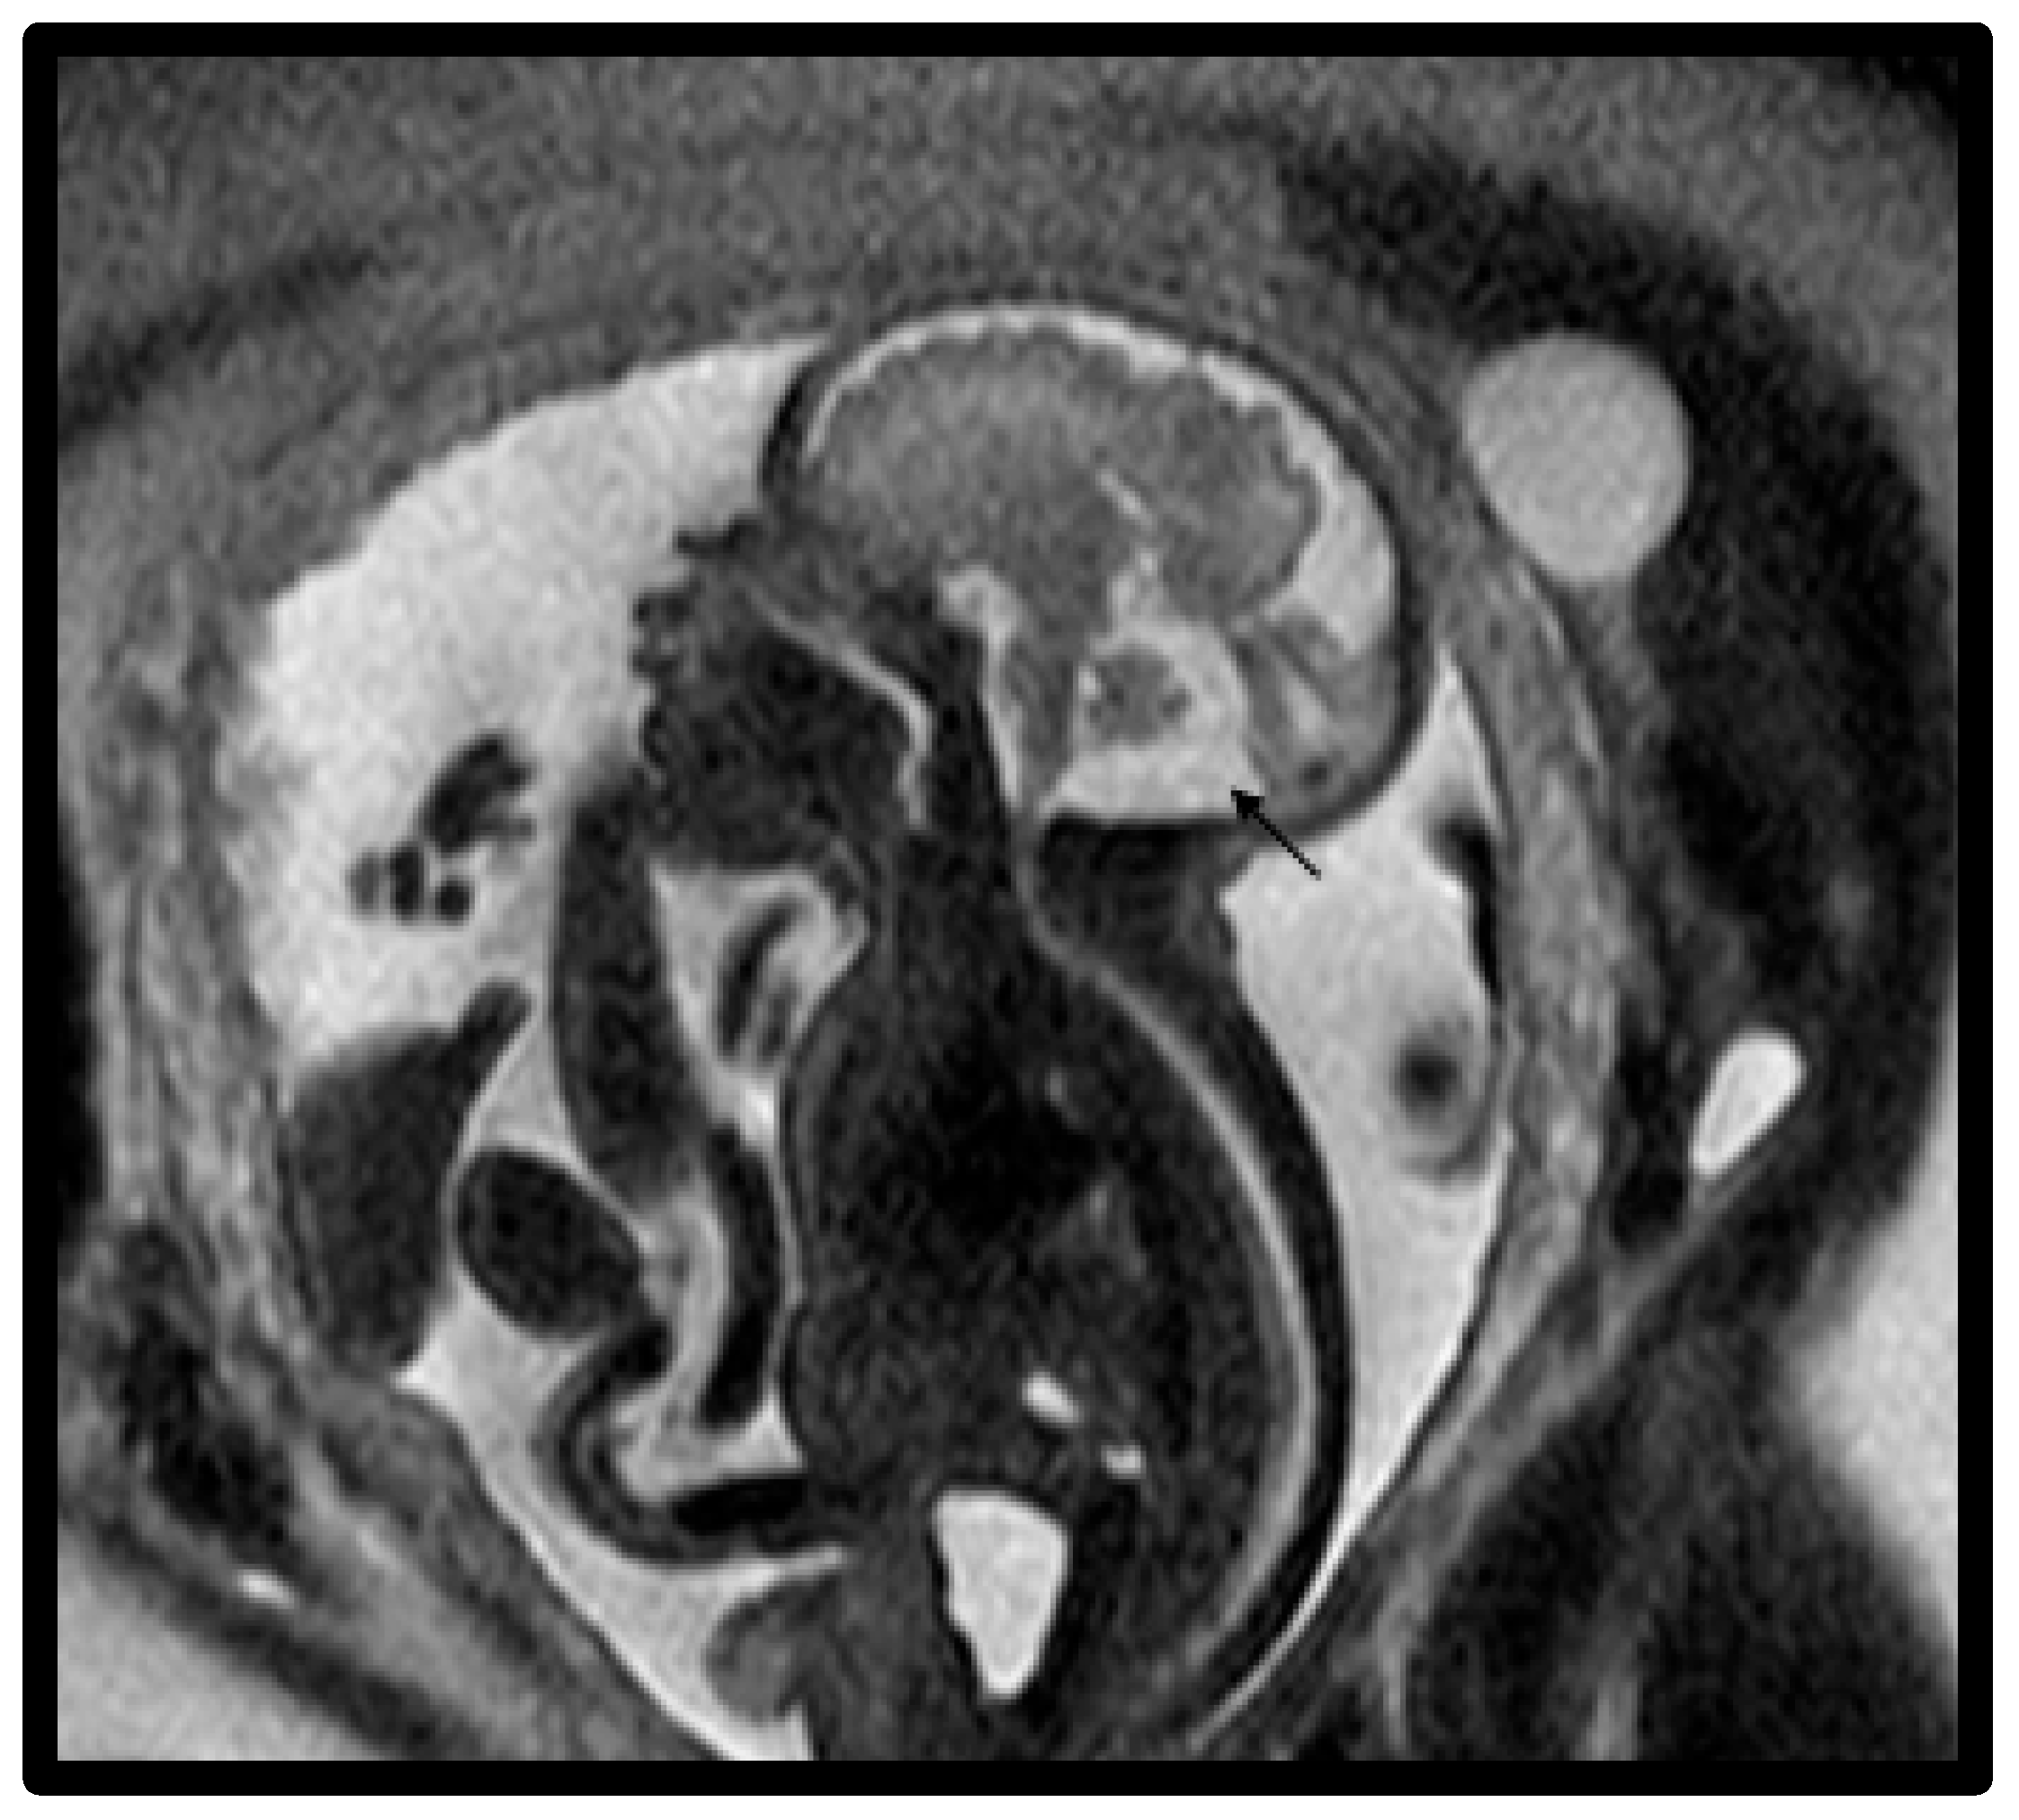

- Whitehead, M.T.; Vezina, G.; Schlatterer, S.D.; Mulkey, S.B.; Plessis, A.J. Taenia-tela choroidea complex and choroid plexus location help distinguish Dandy-Walker malformation and Blake pouch cysts. Pediatr. Radiol. 2021, 51, 1457–1470. [Google Scholar] [CrossRef] [PubMed]

- Paladini, D.; Donarini, G.; Parodi, S.; Volpe, G.; Fulcheri, E. Hindbrain morphometry and choroid plexus position in differential diagnosis of posterior fossa cystic malformations. Ultrasound Obstet. Gynecol. 2019, 54, 207–214. [Google Scholar] [CrossRef] [PubMed]

- Murali, L.; Rangasami, R.; Priyanka, C.; Suresh, I.; Suresh, S. Assessment of fastigial angle in fetuses with Blake pouch cyst and vermian hypoplasia on magnetic resonance imaging. J. Pediatr. Neurosci. 2024, 19, 39–44. [Google Scholar] [CrossRef]